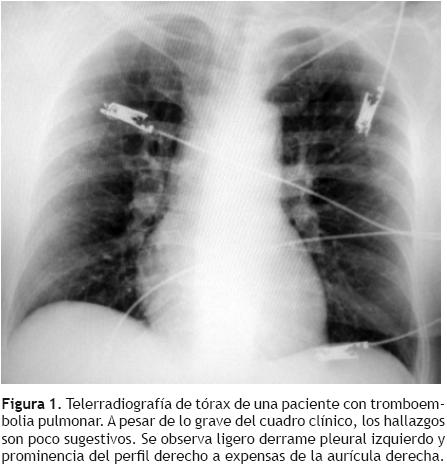

La radiografía de tórax por lo general es normal o presenta signos inespecíficos como atelectasias laminares, elevación del hemidiafragma o derrame pleural (Figura 1). Su utilidad radica en observar otros hallazgos que orienten hacia un problema diferente. Se han descrito algunos signos radiológicos que sólo se presentan en TEP de mayor tamaño como son: la opacidad de la base pleural (joroba de Hampton), elevación del hemidiafragma ipsolateral, amputación de la arteria pulmonar (signo de Palla) y un triángulo de oligohemia focal con base pleural y vértice hacia el hilio pulmonar (signo de Westermark). Estos datos radiológicos se presentan en una minoría de enfermos.17